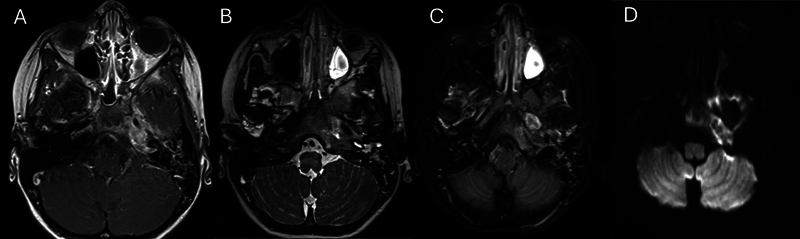

横纹肌肉瘤(Rhabdomyosarcoma, RMS)是一种罕见的恶性肿瘤,每100万儿童中有4.58例发生,约35%发生在头颈部。颅底RMS通常出现在晚期,由于其与其他颅底病理的重叠特征以及难以进入病变进行活检而延误诊断。本病例说明了这些挑战在颅底RMS模拟骨髓炎的岩尖。病例:一名6岁免疫功能正常的女性,有两次急性中耳炎病史,有3周的第6脑神经麻痹史和突然发作的完全性第7脑神经麻痹史。她没有疼痛或耳漏。计算机断层扫描(CT)和磁共振成像显示一个1.3厘米的左岩尖增强病变,延伸到乳突和斜坡,周围的骨和软组织破坏。核医学扫描(锝-99m和镓)显示左侧岩尖摄取旺盛。有效诊断为颅底骨髓炎,为此患者接受了2.5周的抗生素治疗。未能改善后,重复影像学显示疾病明显进展,并扩展到鼻咽和蝶窦。内镜下经蝶窦活检与RMS病理一致。胸部CT示肺转移。患者对用长春新碱、放线菌素- d和环磷酰胺交替使用长春新碱和伊立替康的化疗有部分反应。在化疗的第13周,她接受了总剂量5040 cGyRBE的质子治疗。确诊5个月后,她出现脑膜轻散,并进一步并发脑膜炎,最终去世。

Rhabdomyosarcoma (RMS) is a rare malignant tumor, affecting 4.58 per 1 million children, with approximately 35% occurring in the head and neck. Skull base RMS commonly presents at advanced stages and delays diagnosis due to its overlapping features with other skull base pathology, and difficulty accessing the lesion for biopsy. This case illustrates these challenges in skull base RMS mimicking osteomyelitis of the petrous apex. Case: A 6-year-old immunocompetent female, with a history of two acute otitis media episodes, presented with a 3-week history of sixth cranial nerve palsy and sudden-onset complete seventh cranial nerve palsy. She did not have pain or otorrhea. Computed tomography (CT) and magnetic resonance imaging revealed a 1.3 cm left petrous apex enhancing lesion with extension into the mastoid and clivus with surrounding bony and soft tissue destruction. A nuclear medicine scan (Technetium-99m followed by gallium) demonstrated avid uptake in the left petrous apex. The working diagnosis was skull base osteomyelitis, for which the patient received 2.5 weeks of antibiotics. After failing to improve, repeat imaging showed significant progression of the disease and extension into the nasopharynx and sphenoid sinus. An endoscopic trans-sphenoidal biopsy was performed with pathology consistent with RMS. CT chest revealed lung metastases. The patient partially responded to chemotherapy with vincristine, actinomycin-D, and cyclophosphamide alternating with vincristine and irinotecan. During week 13 of chemotherapy, she received concomitant proton therapy to a total dose of 5040 cGyRBE. Five months after diagnosis, she developed leptomeningeal spread, which was further complicated by meningitis, and passed away.